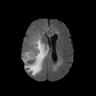

The Flair experiment results are obtained using a training of two cycles in the first stage and four cycles in the second stage to reach the peak separation, and the threshold value is taken at the intensity of 170. For T2 we use two cycles in the first stage and two cycles in the second stage, and the threshold is taken at 220. Both thresholds are taken based on the rightmost peaks of the histograms of reconstructed images. We obtain a subject-wise mean dice score of 79.89% on the Flair scans and 88.57% on the T2 scans. Despite the lower score compared to T2, the Flair modality provides the potential of identifying additional anomalies, which may not be limited to HGG or LGG, as shown in the third column of Fig. 6. However, since the focus of this experiment is to segment HGG and LGG only, using the T2 modality outperforms the Flair in term of the Dice scores as reported in Table 2, and the predicted masks as shown in Fig. 6. Aside from that, on the Flair scans our method suffers both under- and over-segmentation as shown in Fig. 7 and struggles to segment tumors using one uniform threshold as shown in Fig. 8. Typically, we use the rightmost peak as the threshold for brighter tumors; however, the peaks separating tumors in these cases of Fig. 8 occur as the leftmost peak. Such flip further lowers the segmentation score, even though the algorithm is able to separate the anomaly as one of the two cuts.

Although our method has consistently better performance of segmenting brain tumors on T2, as shown from Fig. 6 to Fig. 8. In the case of T2, the primary disadvantages occur due to the inclusion of other regions, such as Cerebrospinal Fluid (CSF), eyeballs, etc., which appear dark in the Flair modality. In order to alleviate these false positives on T2 scans, we multiply the predicted masks with the Flair input images. Then we re-calibrate the output by taking a threshold at the intensity of 50 (roughly 0.2 in the range [0,1]) to generate our final mask. This post-processing is our new choice for the private dataset. We did not use the erosion/dilation operation because it is more efficient for cases with discontinuous segmentation results, which is the one our public datasets suffer with, as shown in Fig. 4, but not our private dataset. This new post-processing improves the performance to a patient-wise mean dice score of 91.58% on T2 scans with two-fold cross validation.